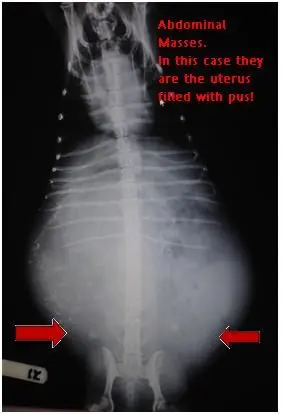

Radiographs help us in many ways.  They help diagnose broken bones, may show possible foreign bodies, bladder stones, masses, abnormalities of heart and lungs and so much more.  This can help pet owners see what is happening inside their animals and help them understand why certain treatment courses are then recommended.

Now it is your turn to give it a try:

Look at these x-rays and guess how they helped the veterinarian make the correct diagnosis.